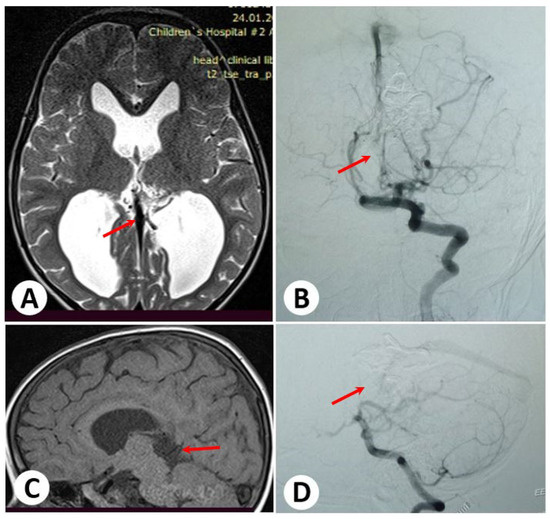

3.1. Illustrative Cases: Case 1

3.2. Illustrative Cases: Case 2